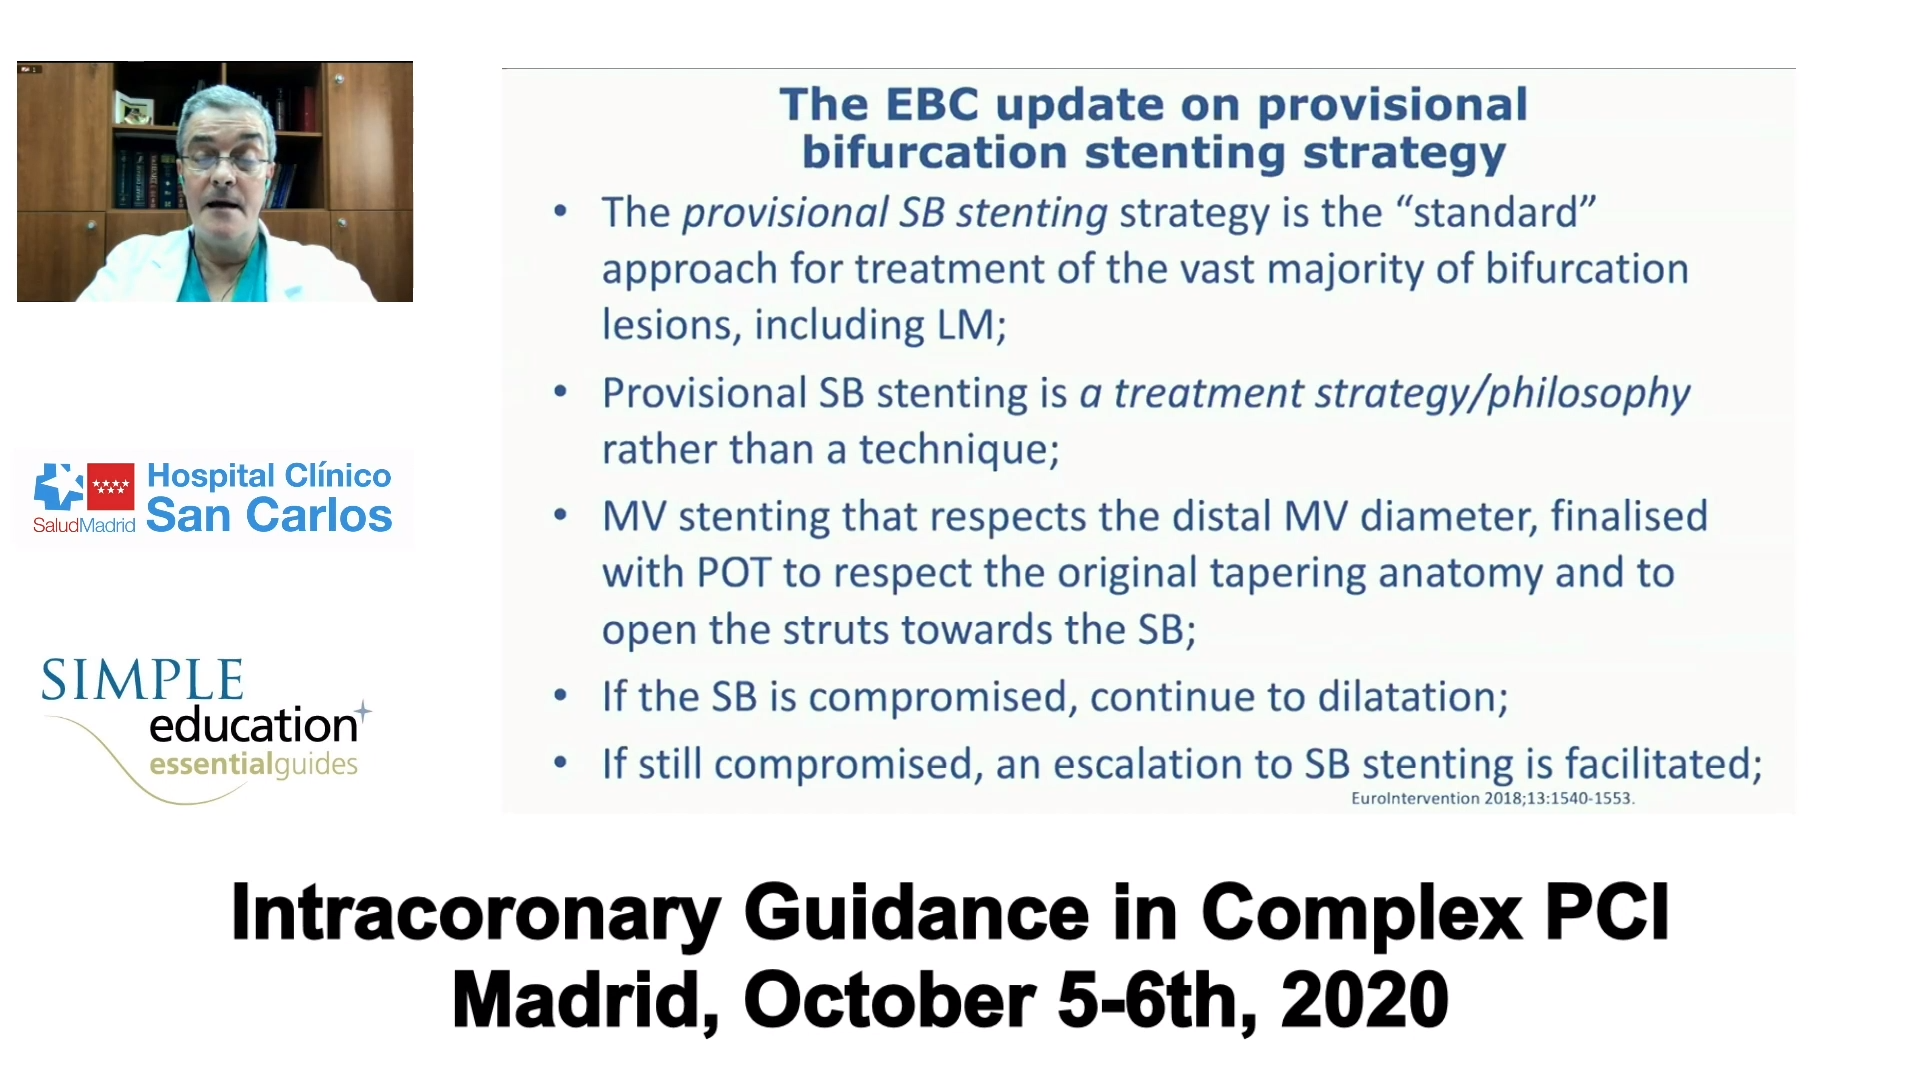

Coronary Bifurcations: An Update on Diagnosis, PCI planning and Imaging and PhysiologyGuidance - Dr Dejan Milasinovic